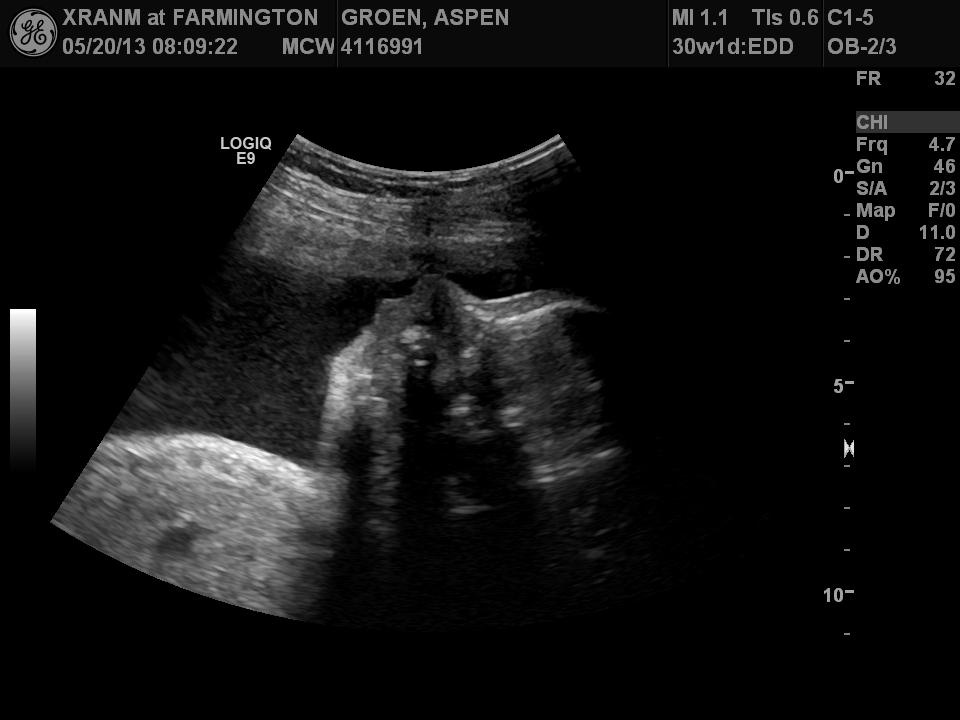

No idea what these measurements mean but I'm sure one day I'll be glad I saved them!

Foster Brady is measuring at 3lbs 3oz (((average is 2.75lbs)))

His heart rate started out at 160! Looks like our little man is getting ready to be born!